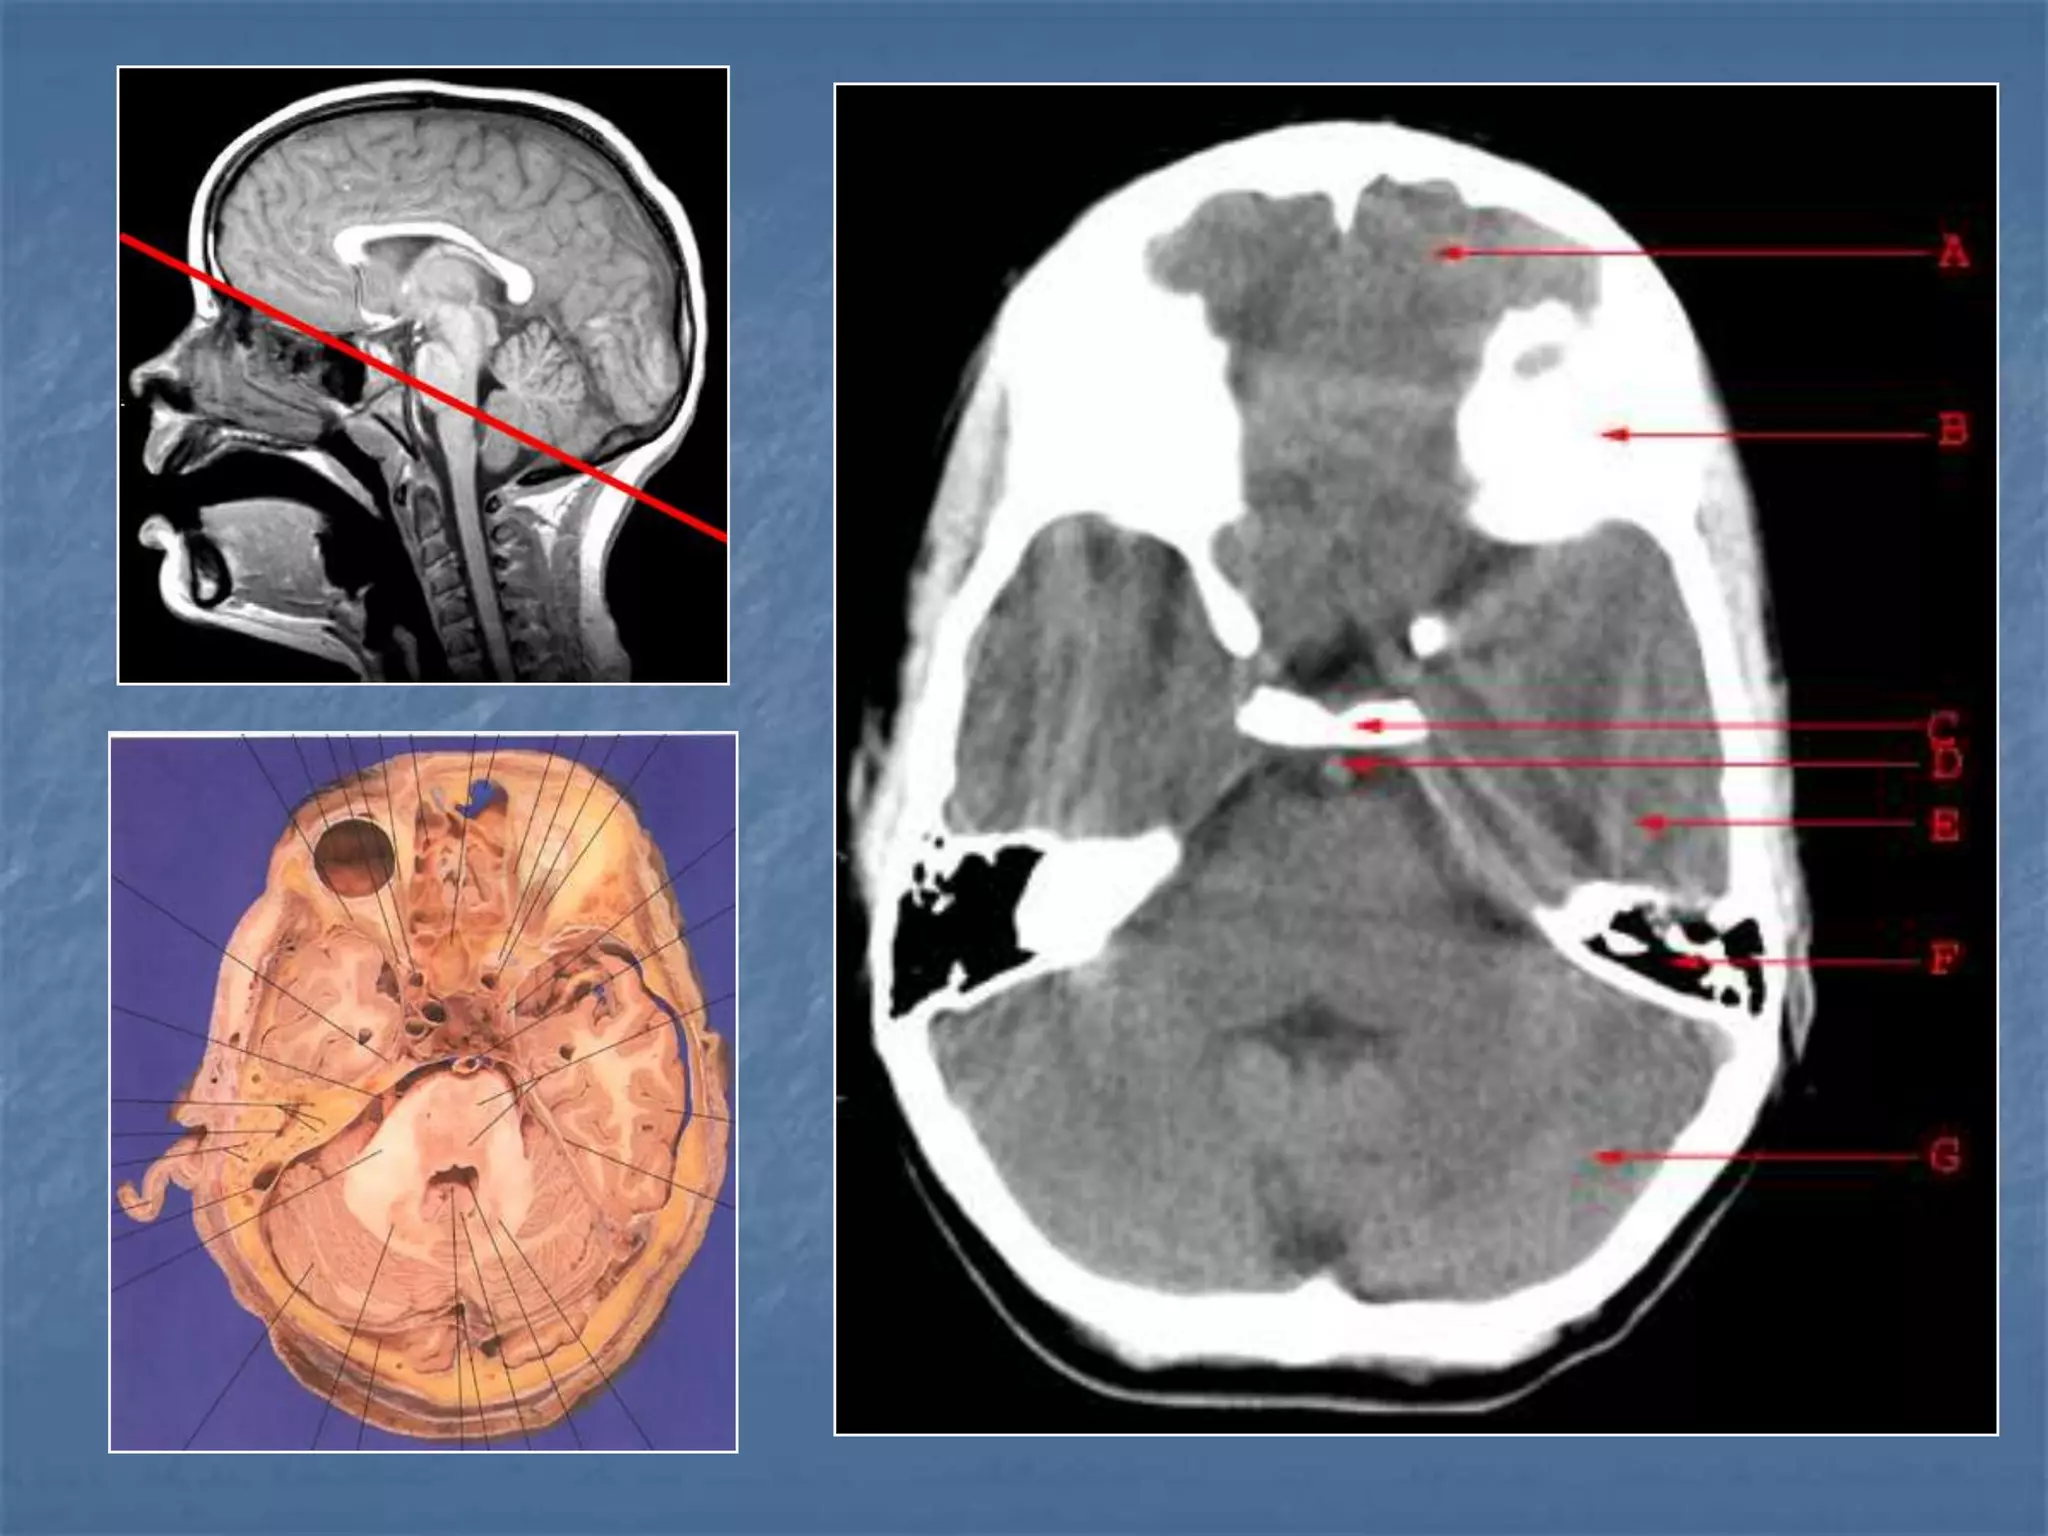

How the CT study is usually planned…

 Thinner sections

are studied

through the

posterior fossa

Hounsfield Units

AIR - - 1000

FAT - - 30 to -100

CSF - 0

GREY MATTER - 32 - 41

WHITE MATTER - 23 - 34

ACUTE BLOOD - 56 - 76

CALCIFICATION - 60 - 400

BONE - 1000